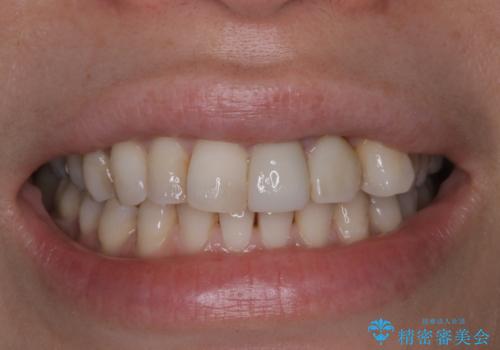

歯の染め出しとPMTCで口腔内ケア

- しばらく歯科でのメンテナンスを受けていないため、歯磨きのチェックとクリーニング希望とのことで来院されました。

染め出しをしてのブラッシング指導とPMTCを行いました。